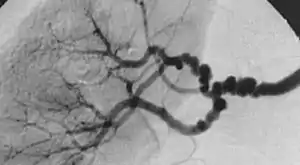

| The "string-of-beads" feature in multi-focal fibromuscular dysplasia. The sign is caused by areas of relative stenoses alternating with small aneurysms. | |

The second type, multi-focal fibroplasia, involves thickening of the media and collagen formation. It is typically reported as having the appearance of a ‘string of beads’ on angiographic review.[4] "The 'bead' component is often larger than the normal arterial lumen, and in a subset of patients with FMD, aneurysms are present that may require treatment." [4] The multi-focal subtype of FMD accounts for nearly 80% to 90% of all FMD cases.[4] (previously known as medial)